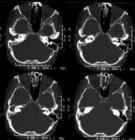

中耳炎鼓膜穿孔流脓后症状体征反而加重者,多为突感染所致。乳突X线摄片或CT扫描,可见乳突区混浊或有骨质破坏。

急性期治疗同急性化脓性中耳炎,如经合理治疗一个月不见好转,或高热体温不下,耳后红肿,外耳道后壁塌陷,乳突X线摄片有骨质破坏,应采用简单乳突凿开术治疗。